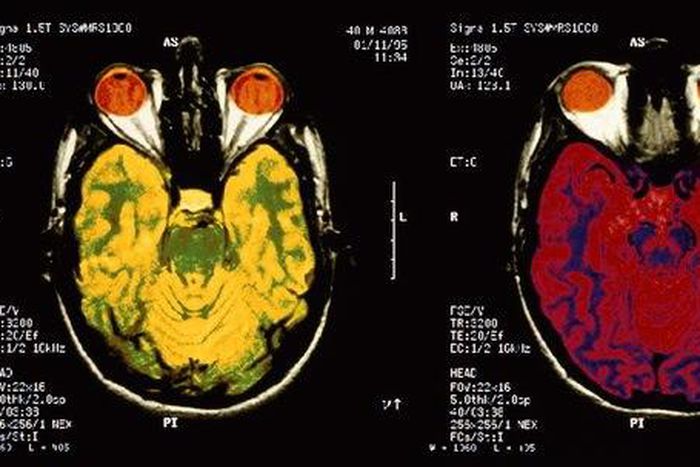

Studies published this year shed light on the mysteries of the brain and human behavior, and began paving the way for new treatments to mental and neurological health problems, ranging from addiction to autism to Alzheimer's disease.